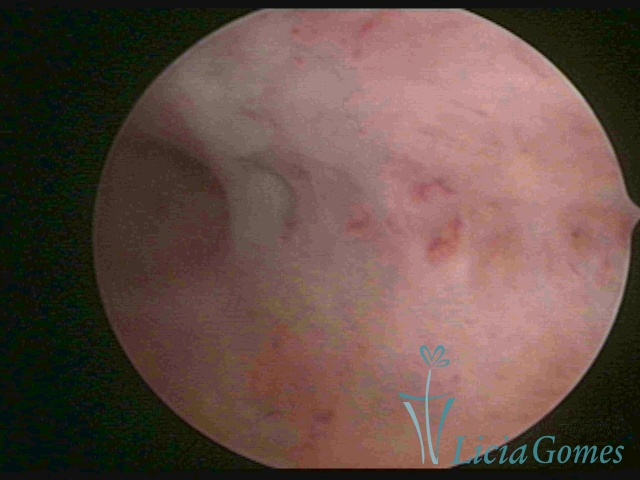

In video hysteroscopy, we observe the endometrium bleeding, its endometrial surface is speckled, presenting a “creamy” aspect and a whitish color with a brightness enhanced by the fibrin accumulated. Bluish or rough areas, which may correspond to cystic necrosis. The presence of adhering mucus or pyometra may occur.

The surface of the endometrium may present changes such as a red punctuate forming vascular balls, a smooth, hypervascularized endometrium or intensely presenting red areas, with accurate edges and yellowish white spots in its interior, providing a "STRAWBERRY PEEL" aspect, a pale yellow color of fundic and lateral commissures, in contrast with the intense red color present in the walls.